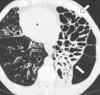

12

A

Consolidación alveolar